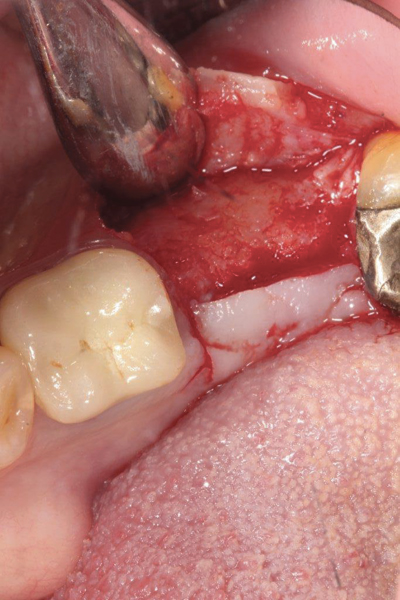

Fig 1. (Case 1) Tooth No. 19 manifested a buccal fistulous tract. Probing depth on the buccal was 8 mm.

Figure 1

Fig 2. Buccal flap elevated exposing buccal plate defect.

Figure 2